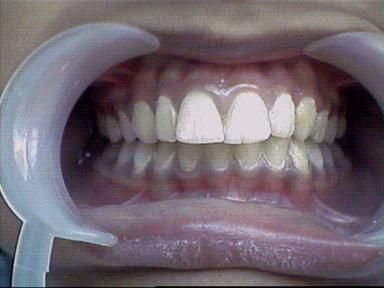

After Treatment Intra Oral